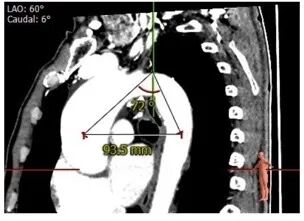

术前陈晓敏教授带领团队对这位患者进行了详细的分析,从CT分析结果显示,患者主动脉瓣为type 0型二叶瓣,瓣环直径为24.4mm,结合患者瓣叶钙化等情况,符合美敦力Evolut PRO 29mm瓣膜选型。经讨论决定以右侧股动脉为主入路,左侧股动脉为辅入路,术中进行23mm球囊预扩张,保证系统顺利跨瓣及释放,并采用世界先进的Cusp Overlap技术植入瓣膜 ,以更精准地释放瓣膜深,减少对患者传导系统的影响。